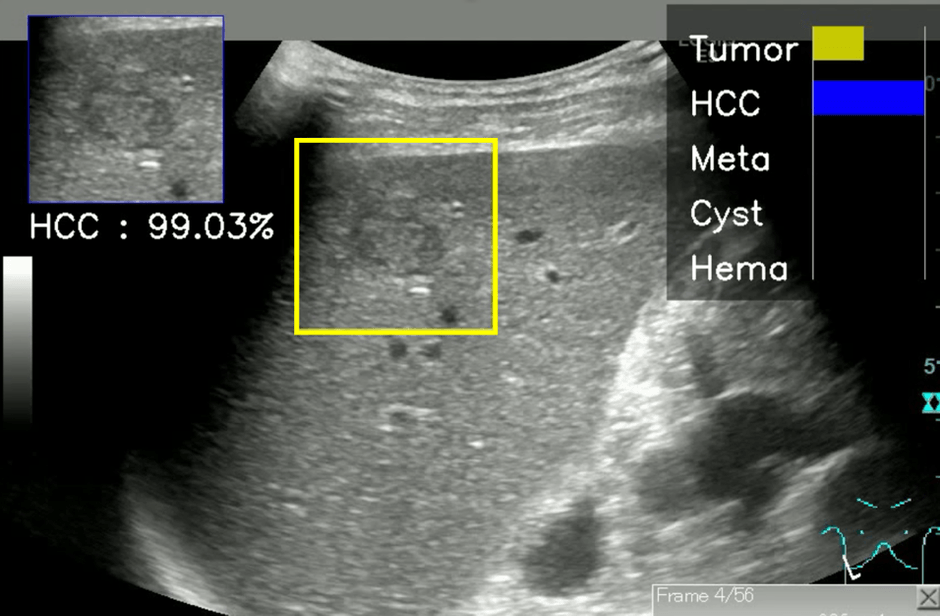

遭遇頻度の高い4種類の肝腫瘤のBモード超音波画像70,950枚を、ディープニューラルネットワークの一種である、19層の畳み込みニューラルネットワーク※4 に学習させました。Bモード超音波画像の腫瘤部を正方形に切り出して、4種類の学習画像数がおよそ等しくなるようにデータ拡張を行い、10分割交差検証法※5 にて評価しました。学習データ数の増加に伴い、全体の正診率、疾患ごとの鑑別精度、良悪性の鑑別精度、悪性腫瘍検出の感度、特異度は順調に上昇し、最終的に70,950画像の学習AIモデルでは、4種類の疾患の鑑別精度は91.1%、悪性腫瘍鑑別精度は94.3%(感度:82.8%、特異度:96.7%)であり、高い鑑別能を示しました。

本研究では、テスト用肝腫瘤動画を用いて、AIと熟練医の診断能の比較も行っています。AIの診断にはBモード超音波の動画から5フレームの静止画を選び、3フレーム以上で一番高い推定確率を示す疾患をAIの診断としました。一方、ヒトは静止画のみから診断することは通常極めて困難なため、動画を観察して診断しました。この結果、AIの4疾患鑑別精度は89.1%、悪性腫瘍鑑別精度は90.9%であったのに対して、熟練医5名の4疾患鑑別精度の中央値は67.3%(分布:63.6%~69.1%)、悪性腫瘍鑑別精度の中央値は80.0%(分布:74.5%~83.6%)であり、AIの精度が熟練医の結果を大きく上回りました。また、正しい診断に対するAIの推定確率は、学習データ数が多いほど上昇しており、これはAIが学習を増やすことにより信頼性の高い正解を出力できることを示しています。肝腫瘤のBモード超音波診断において、本AIモデルを活用することにより、非専門医においても熟練医を上回る診断を行うことができると期待されます。